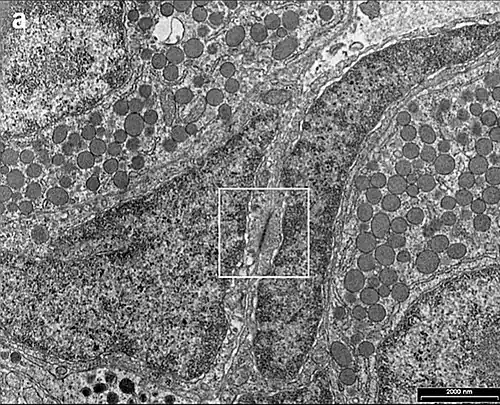

Ultraestructura

Con el microscopio electrónico (ME) las células gonadotropas muestran las características propias de las células secretoras de polipéptidos. Un retículo endoplasmático rugoso con sacos dilatados. Un gran número de vesículas secretoras densas entre 300-400 nanómetros (nm).[9][10]

Las numerosas mitocondrias en el citoplasma, son reflejo del elevado consumo de energía.[8]

Los núcleos son habitualmente redondeados, de aspecto claro por la eucromatina predominante y están colocados excentricamente en la célula.[11]

Son visibles las uniones gap comunicantes, que facilitan y regulan la actividad, coordinando las respuestas de las células conectadas y por tanto la función secretora gonadótropica.[12][13]